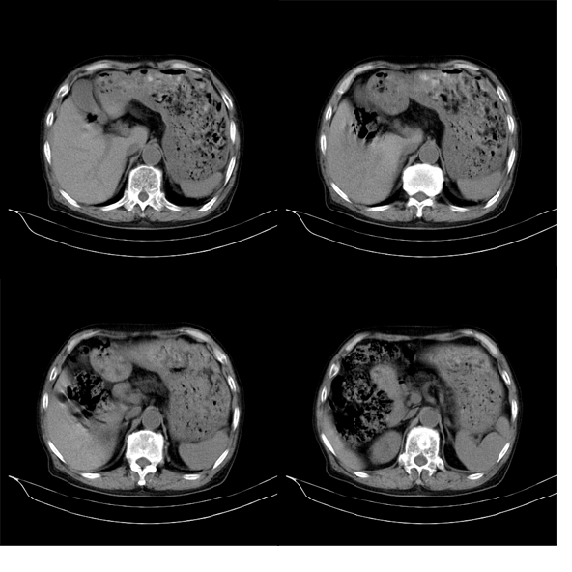

m79y自述30年前做过疝手术,20年前间断出现尿血,每次经抗炎治疗后即好转,近一月来又出现尿血但抗炎后仍尿血.现做双肾+盆腔ct:

双肾10mm扫描

1.膀胱内软组织肿快,有点状钙化,前列腺不大.膀胱癌.

3.双肾平扫未见异常.